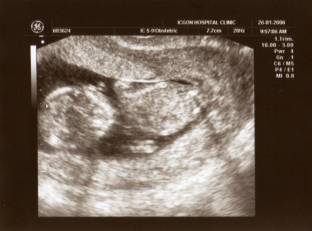

J’ai été conçu en novembre 2005 à Milan, après un spectacle mémorable à la Scala, dans un salon plein de trophées africains et de fétiches divers... Mon papa et ma maman se sont aperçus de ma présence au retour d’un voyage à Paris, et la veille de notre départ à Cuba – déjà, ma vie était placée sous l’étoile des voyages… Au retour de Cuba, alors que je n’avais que 12 semaines, on a fait la première échographie à maman. Et voilà le résultat :

Ça, c’est moi de dos dans le ventre de maman (en réalité, il faudrait basculer la photo car ma tête regarde vers le bas). Les deux points sur la droite, ce sont mes fémurs.